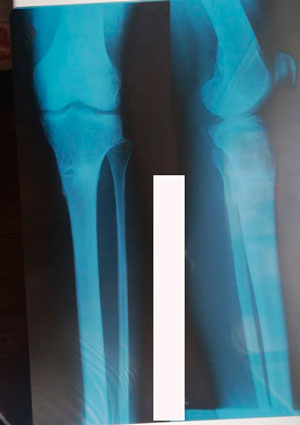

Исходник - 38 лет.

Дата операции - 07.11.2019г.

Диагноз: Варусная деформация голеней. Ротация справа.